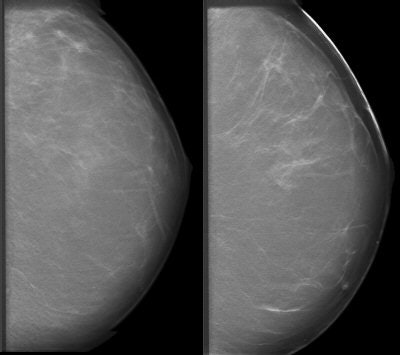

"DBT addresses one of mammography's important weaknesses, which is that of overlapping tissue," explained Joseph Lo, Ph.D. "It can obscure a lesion that is already there, because things are all pancaked together in a conventional mammogram. DBT can also help to better characterize lesions that you do see."

![]() |

| Above, conventional mammogram on which cancer is obscured. Below, DBT slice on which cancer is clearly defined. Images courtesy of Richard Moore and Dr. Daniel Kopans. |